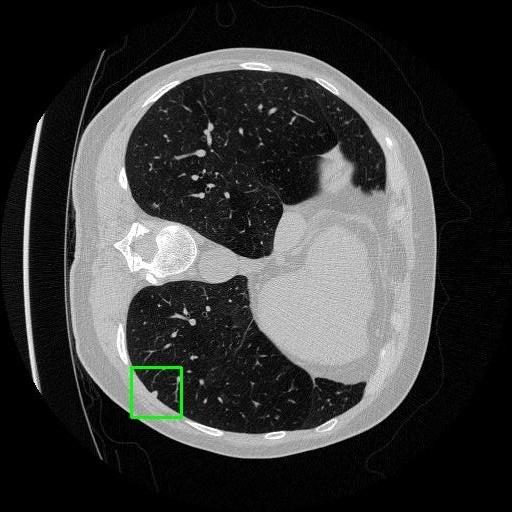

We developed an AI-based system using deep learning models for analyzing lung CT scans to detect and classify pulmonary nodules. We chose the YOLOv11 architecture for its enhanced object detection capability and adapted it specifically for medical imaging, incorporating pixel-level precision and severity classification.

Classification into three severity levels with colored bounding boxes.

Designed a severity classification system that categorizes nodules into null, moderate, and severe using colored bounding boxes, assisting in rapid clinical decision-making.